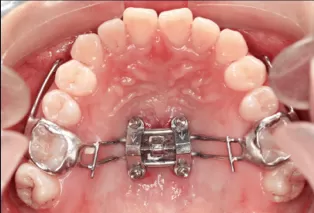

In Treatment

Intraoral photos